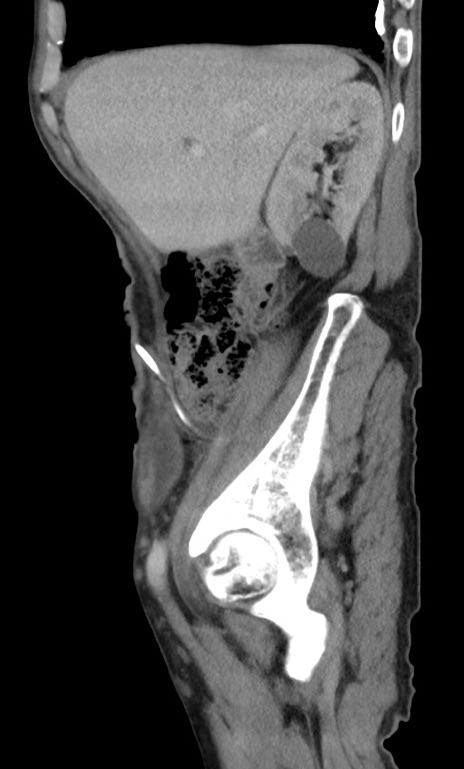

症例3(矢状断像)

【症例】 70歳代男性

【主訴】右鼠径部腫瘤、疼痛

【現病歴】本日朝より上記主訴あり、受診。

【既往歴】膀胱癌にて膀胱全摘、両側尿管皮膚瘻

【データ】WBC 5600、CRP 0.56